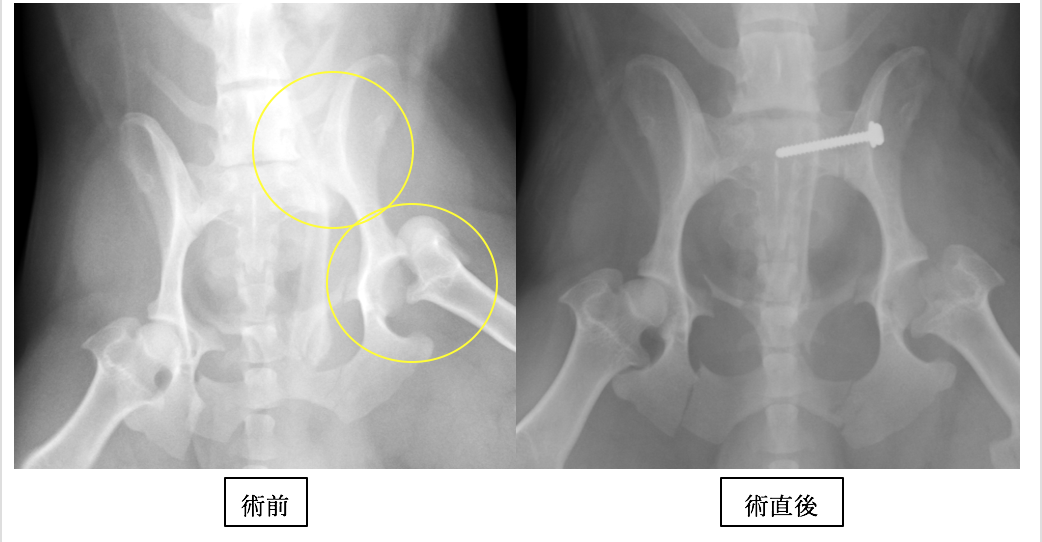

M・ダックスフンドです。痛みが強かったのですが、術後は骨折前と同じように活動できています。

数カ所折れていますが、重要なのは仙腸関節(上の◯)の脱臼と、股関節脱臼です。

仙腸関節はラグスクリュー法と呼ばれるスクリューによる固定を行い、股関節は大腿骨頭切除術と呼ばれる方法を行っています。